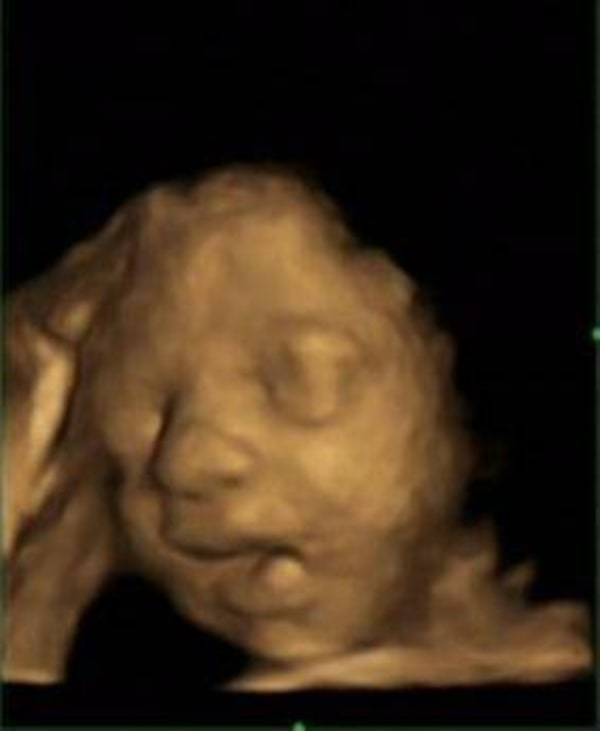

Ultrasound scans of faces in utero can distinguish between when a fetus yawns and when it just opens its mouth, says study published by PLOS ONE.

Until recently, however, many researchers believed that fetuses who looked like they were yawning were simply opening their mouths wide. But a new study published Wednesday in the journal PLoS One suggests fetal yawning can be reliably distinguished from a gaping mouth.

In the study, 15 healthy fetuses were scanned four times at 24, 28, 32 and 36 weeks gestation. A technician did 10-minute sessions of 4D ultrasound, which produces multidimensional images of the fetus in motion.